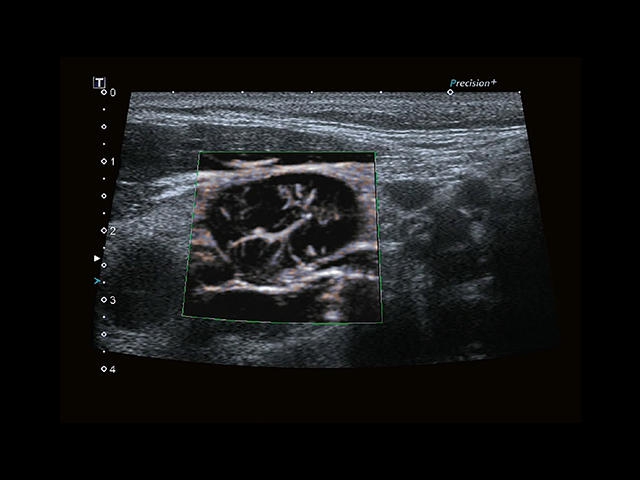

Aplio 500 – ультразвуковой сканер премиум класса, сочетающий в себе быстродействие диагностики и отличное качество визуализации. Более 30 датчиков на выбор, в т.ч. матричные, монокристаллические, 4D, эндоскопические для любых типов исследований. Ультразвуковой сканер позволяет изучать анатомические структуры в высоком разрешении.

Обновленная версия легендарного УЗ-сканера. Стационарный аппарат экспертного класса Aplio 500 Toshiba NEW, визуализирует анатомические структуры в высоком разрешении. Модель позволяет выявить микрокальцификаты, новообразования, нарушения в работе сердца, сосудов и мышц. Присутствует функция виртуальной эндоскопии, 4D-сканирования, эластометрии тканей, УЗИ с контрастированием. За повышение качества изображения отвечают технологии ApliPure и Superb Microvascular Imaging. Первая задействует возможности пространственного и частотного кодирования, формирует цельный визуальный ряд с сохранением клинических маркеров. Вторая улучшает отображение микрососудистого русла, используя доплеровский эффект. Модель оснащена 21-дюймовым монитором, имеет 4 активных порта. Возможно подключение педиатрических, интраоперационных, лапароскопических и чреспищеводных датчиков.

• MicroPure. Высокотехнологичное решение в области выявления микрокальцификатов – маркеров новообразований злокачественного типа. Маркеры идентифицируются путем изучения затененных изображений целевого участка. Микрокальцификаты отображаются в виде белых пятен.

• SMI. Опция, упрощающая визуализацию микроциркуляторного русла. С ее помощью обследуются сосуды с низкой интенсивностью кровотока, изучаются наиболее тонкие структуры. SMI упрощает диагностику новообразований, минимизирует вероятность ошибки.